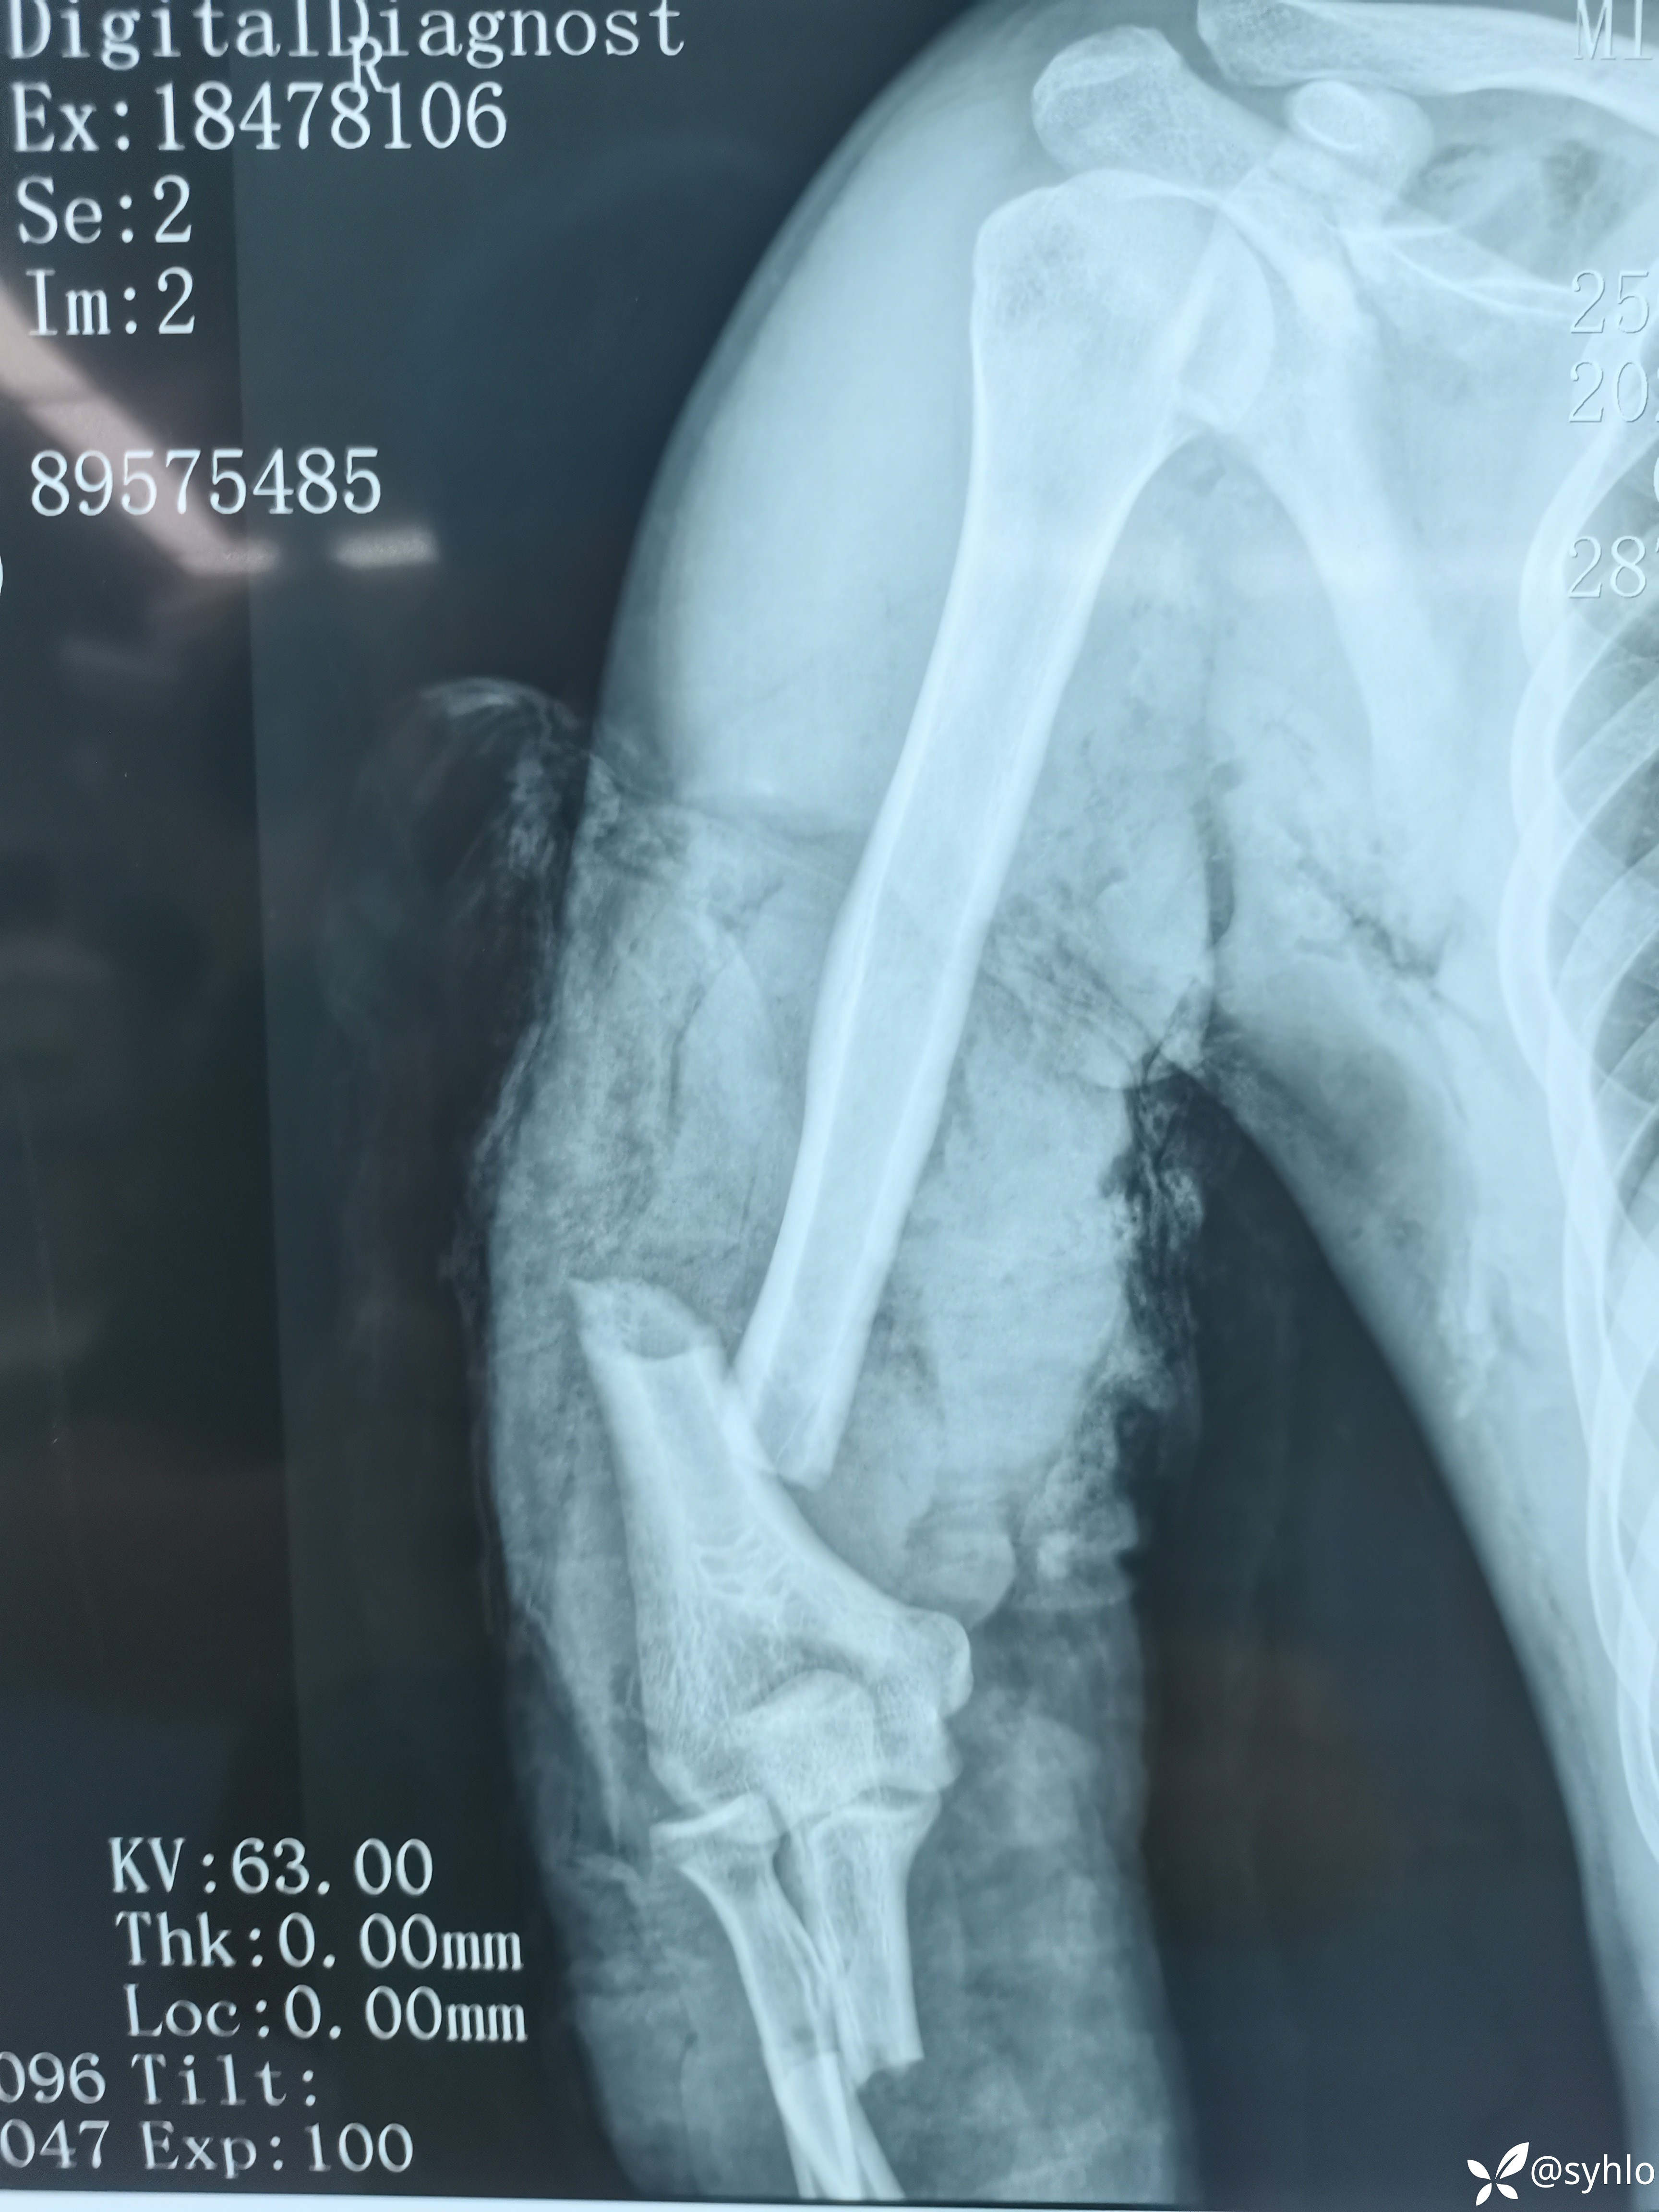

机器搅伤右上肢,缅甸籍贯在中国打工,家庭十分困难,多地辗转建议转省级医院治疗,家庭困难不愿意转。开放性肱骨,尺桡骨,掌骨骨折伴皮肤大面积撕脱。急诊清创外固定架+VSD负压吸引